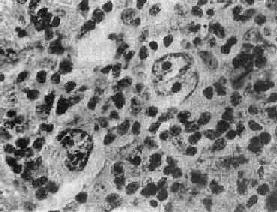

镜下,淋巴结的正常结构破坏消失,由瘤组织取代。瘤组织内的细胞成分多样,有些是肿瘤成分,有些是非肿瘤成分。瘤组织中有一种独特的多核瘤巨细胞,体积大,直径约15~45μm,椭圆形或不规则形;胞浆丰富,双色性或呈嗜酸性;核大,可为双核或多核,染色质常沿核膜聚集成堆,核膜厚。核内有一大的嗜酸性核仁,直径约3~4μm,周围有一透明晕。这种细胞称为Reed-Sternberg细胞(R-S细胞)。双核的R-S细胞的两核并列,都有大的嗜酸性核仁,形似镜中之影故称镜影细胞(图11-1)。这些双核和多核的R-S细胞是诊断HD的重要依据。

图11-1 何杰金病示镜影细胞